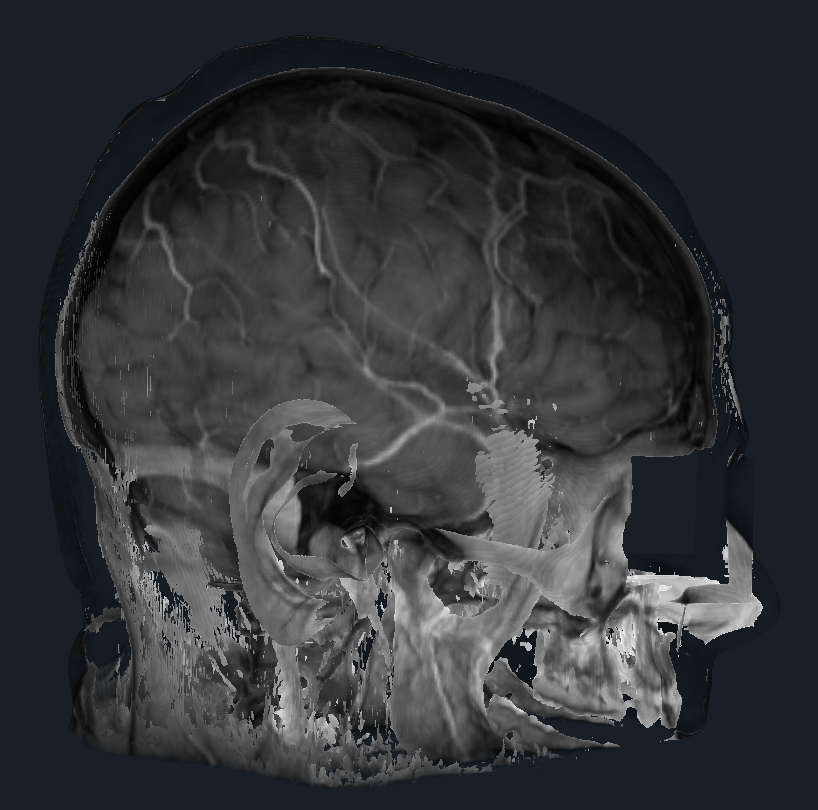

- Provided a proof of concept (python script) for dynamic shader editing in Slicer (see image, video and link to script below)

Proof of concept

Result

Illustrations

| Philips 3D US | Chroma-depth in PRISM | Depth peeling in PRISM |

|---|---|---|

|

|

|

| Edge enhancement in PRISM | Decluttering in PRISM | Volume carving in PRISM |

|---|---|---|

|

|

|

| Blood flow animation in PRISM | ||

|---|---|---|

|